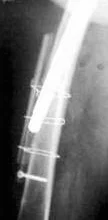

При стоянии или ходьбе на эндопротез ложится большая нагрузка, в соединении между костью и эндопротезом происходят микродвижения. Вследствие этого эндопротез расшатывается. Может расшататься как ножка (бедренный компонент), так и чашка (вертлужный компонент) протеза. Ножка эндопротеза может разрушить стенку кости, в которой расположена - возникает перипротезный (парапротезный) перелом.

При перипротезном переломе потребуется операция остеосинтеза с последующим длительным ограничением физической активности.